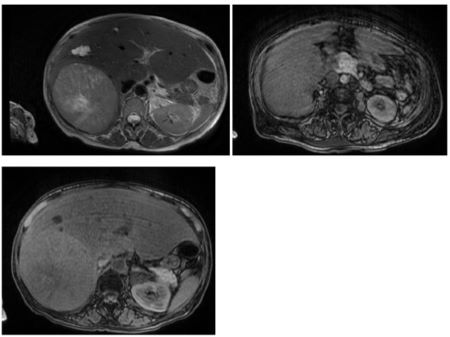

Se observa tumor de gran tamaño en el lóbulo derecho hepático – 14 x 10 cms

Resonancia magnética de abdomen. Se realizó resonancia magnética de abdomen y pelvis con contraste endovenoso para mayor estudio y localizacion del tumor. Se observa en lobulo derecho hepático masa voluminosa (14 x 10 mm), con realce heterogeneo, centro necrótico. Además, presentaba quistes de menor tamaño. En cuerpo de páncreas se observaba lesion nodular con realce heterogéneo sugestivo de malignidad. En suprarrenal izquierda se observaba lesión nodular con realce heterogéneo de 31 mm de diámetro máximo sugestiva de secundarismo

Tomografía de tórax y abdomen superior. Se realizó tomografía de tórax ante la sospecha de metastasis pulmonar. En lóbulo inferior derecho presentaba nódulo de bordes irregulares parahiliar de 22 mm de diametro máximo, altamente sugestivo de secundarismo. Múltiples imágenes ganglionares mediastínicas.